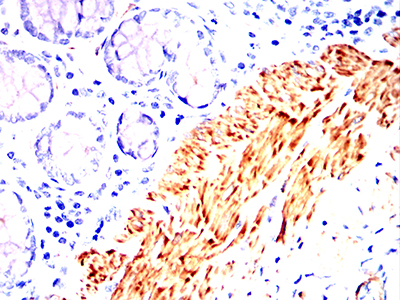

| IHC | 1/50-1/100 | Human,Mouse,Rat |

Antibodies targeting α-SMA are widely used in research and diagnostics to identify smooth muscle-containing tissues and pathological conditions involving myofibroblast activation. In histopathology, these antibodies help distinguish vascular lesions, stromal tumors, and fibrotic processes. They are particularly valuable in cancer research for detecting cancer-associated fibroblasts (CAFs) in tumor microenvironments and assessing fibrotic progression in organs like the liver, lungs, and kidneys.